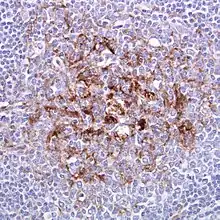

Biopsy of the tonsil in variant CJD. Prion protein immunostaining.